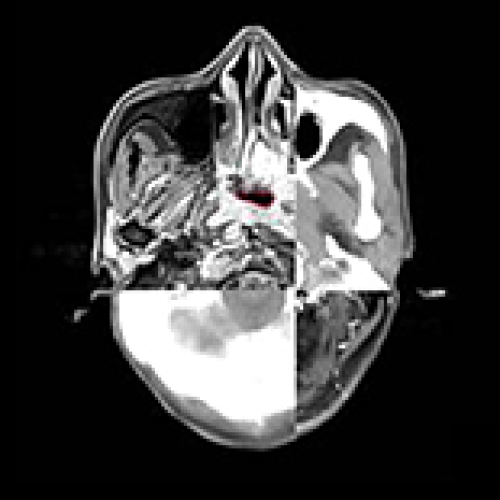

12 Nov 2018 : Clinical Research

Clinical Study on Complications of Intracranial Ruptured Aneurysm Embolization by Stent-Assisted Coil

Yinlong Liu, Jianren Wang

DOI: 10.12659/MSM.911773

Med Sci Monit 2018; 24: CLR8115-8124